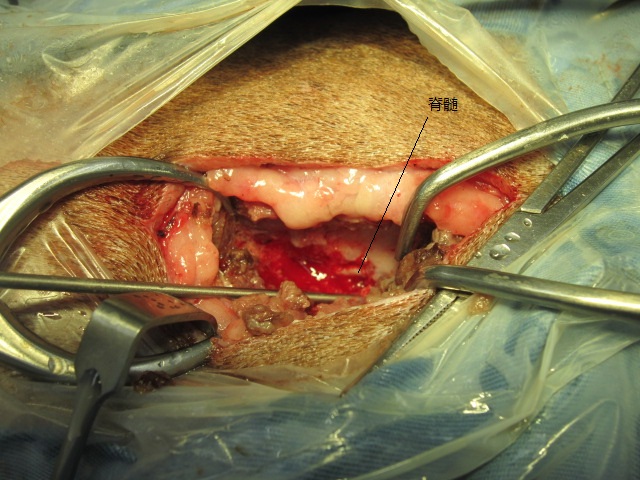

手術中の様子です。

椎弓を切除すると、大量の椎間板物質がでてきました。

椎間板物質除去後です。

脊髄が見えるようになりました。

神経症状を早期に回復するためには、できるだけ早く圧迫物質を取り除くことが必要です。